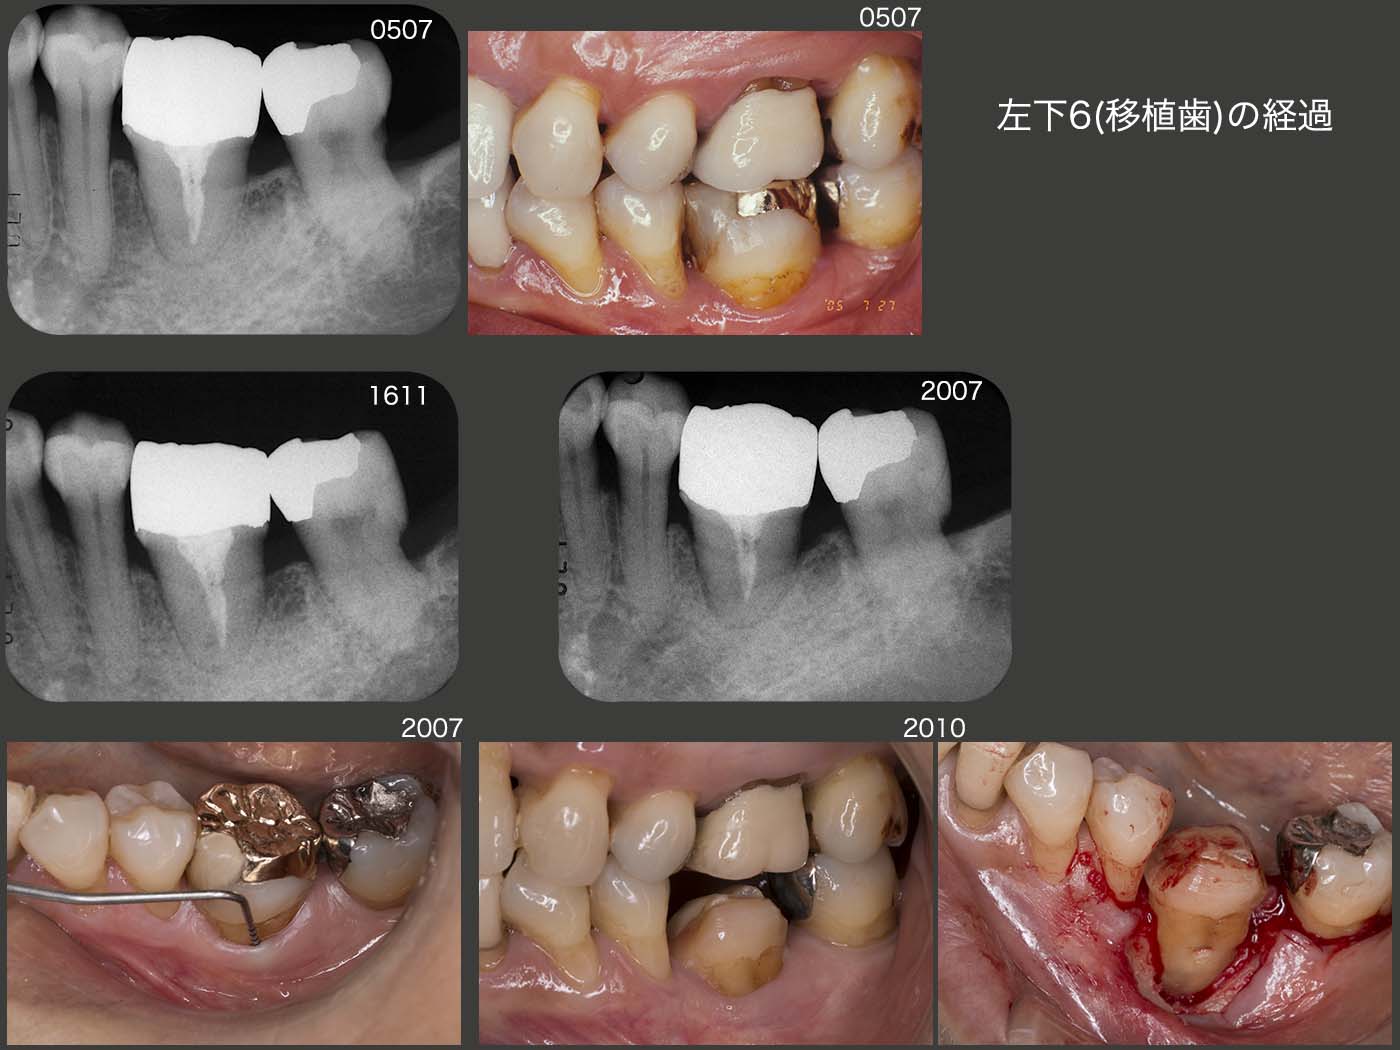

移植された左下6の経過であるが,2005年7月から19年12月までは,良好に経過した.(中段のデンタルX線写真は16年11月時).しかし,右下5を失い,左側で咀嚼する頻度が高くなったことが原因と思われるが,20年7月,頰側の歯周ポケットが10mmの値を示すようになってしまった.クラウンを外し,3ヵ月間自然挻出を期待したが,あまり変化がみられなかった.10月に歯周外科を施したが,頰側の骨が全く存在しなかった.12月現在,経過観察中であるが,歯周ポケットの改善(上皮性付着の獲得)がみられれば,左下7と連結固定(2次固定が望ましい)するつもりである.21年3月,左下5にクラスプ,左下6,7にコーヌス冠を用いた可撤式補綴装置の印象を採得した.